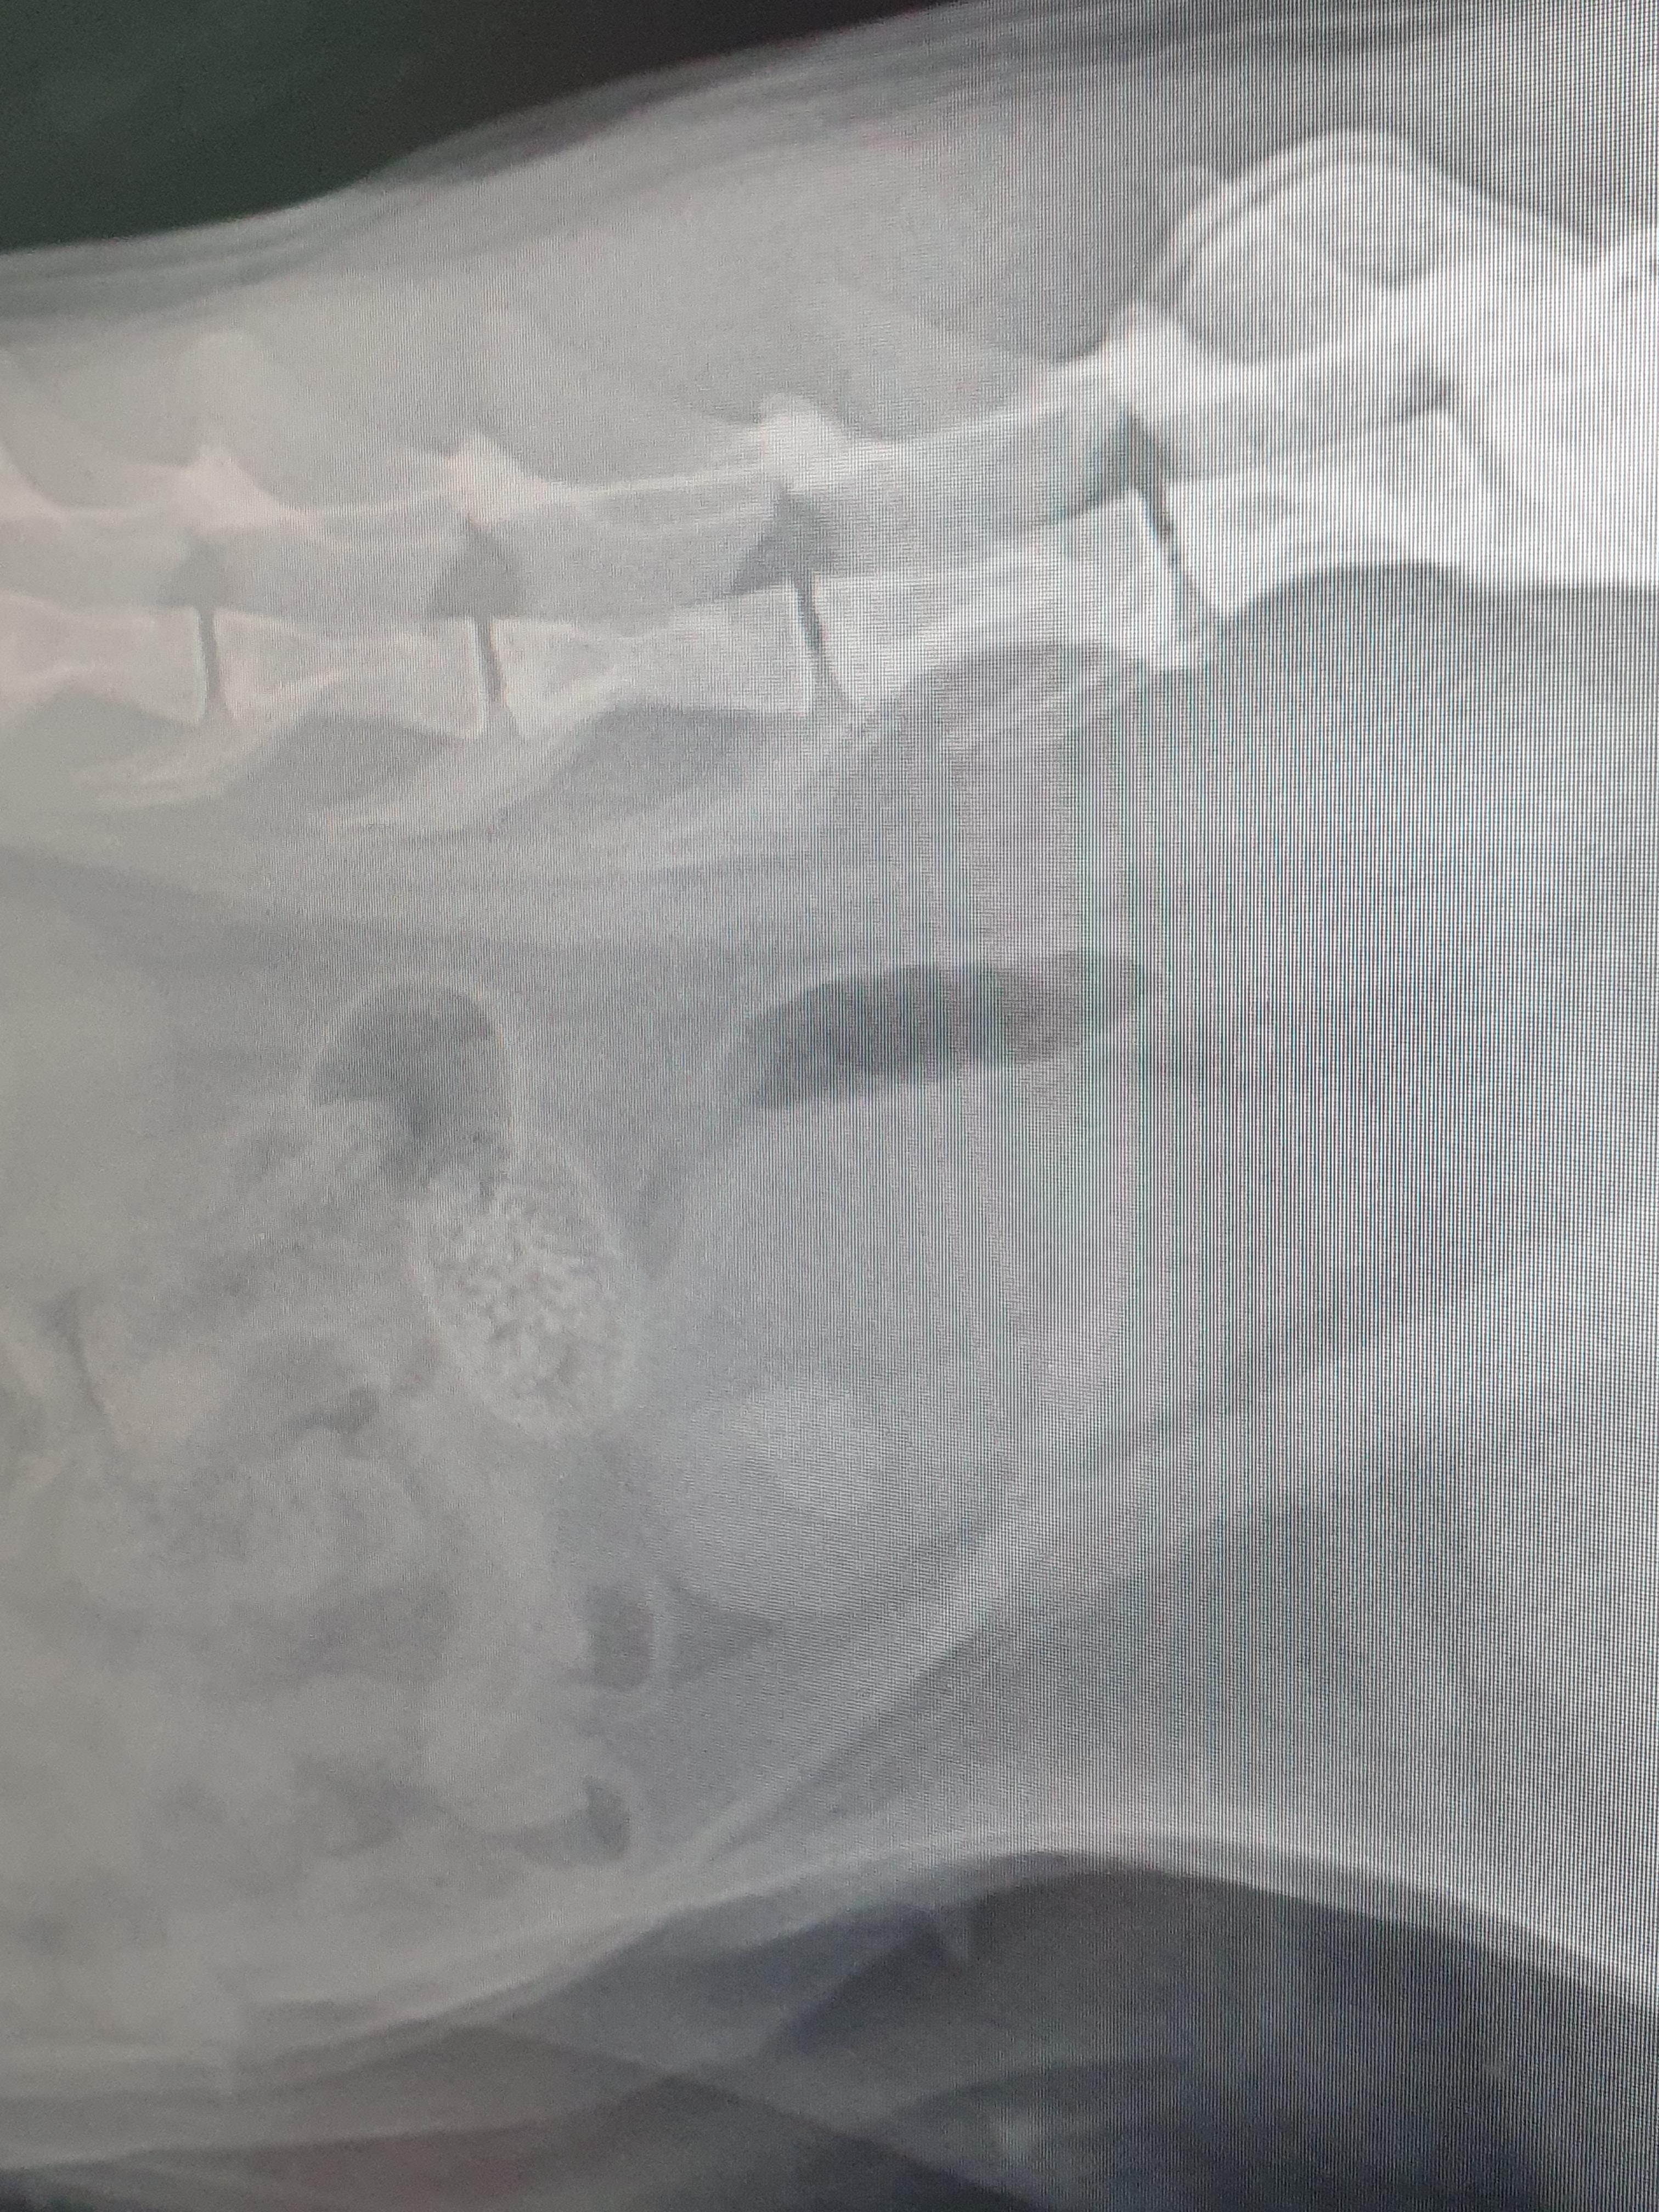

안고 들어가서 방광초음파와 엑스레이를 찍고 나왔다.

초음파에 약 0.9mm 사이즈의

결석이 발견됐다고 하셨다.

거의 1cm가 되는 결석이라니

엑스레이상으로도 너무 또렷이 보였다.

결석은 크게 두가지로 나뉘는데,

약물이나 처방사료로 녹을 수 있는 스투르바이트와

녹지 않는 칼슘옥살레이트 이다.